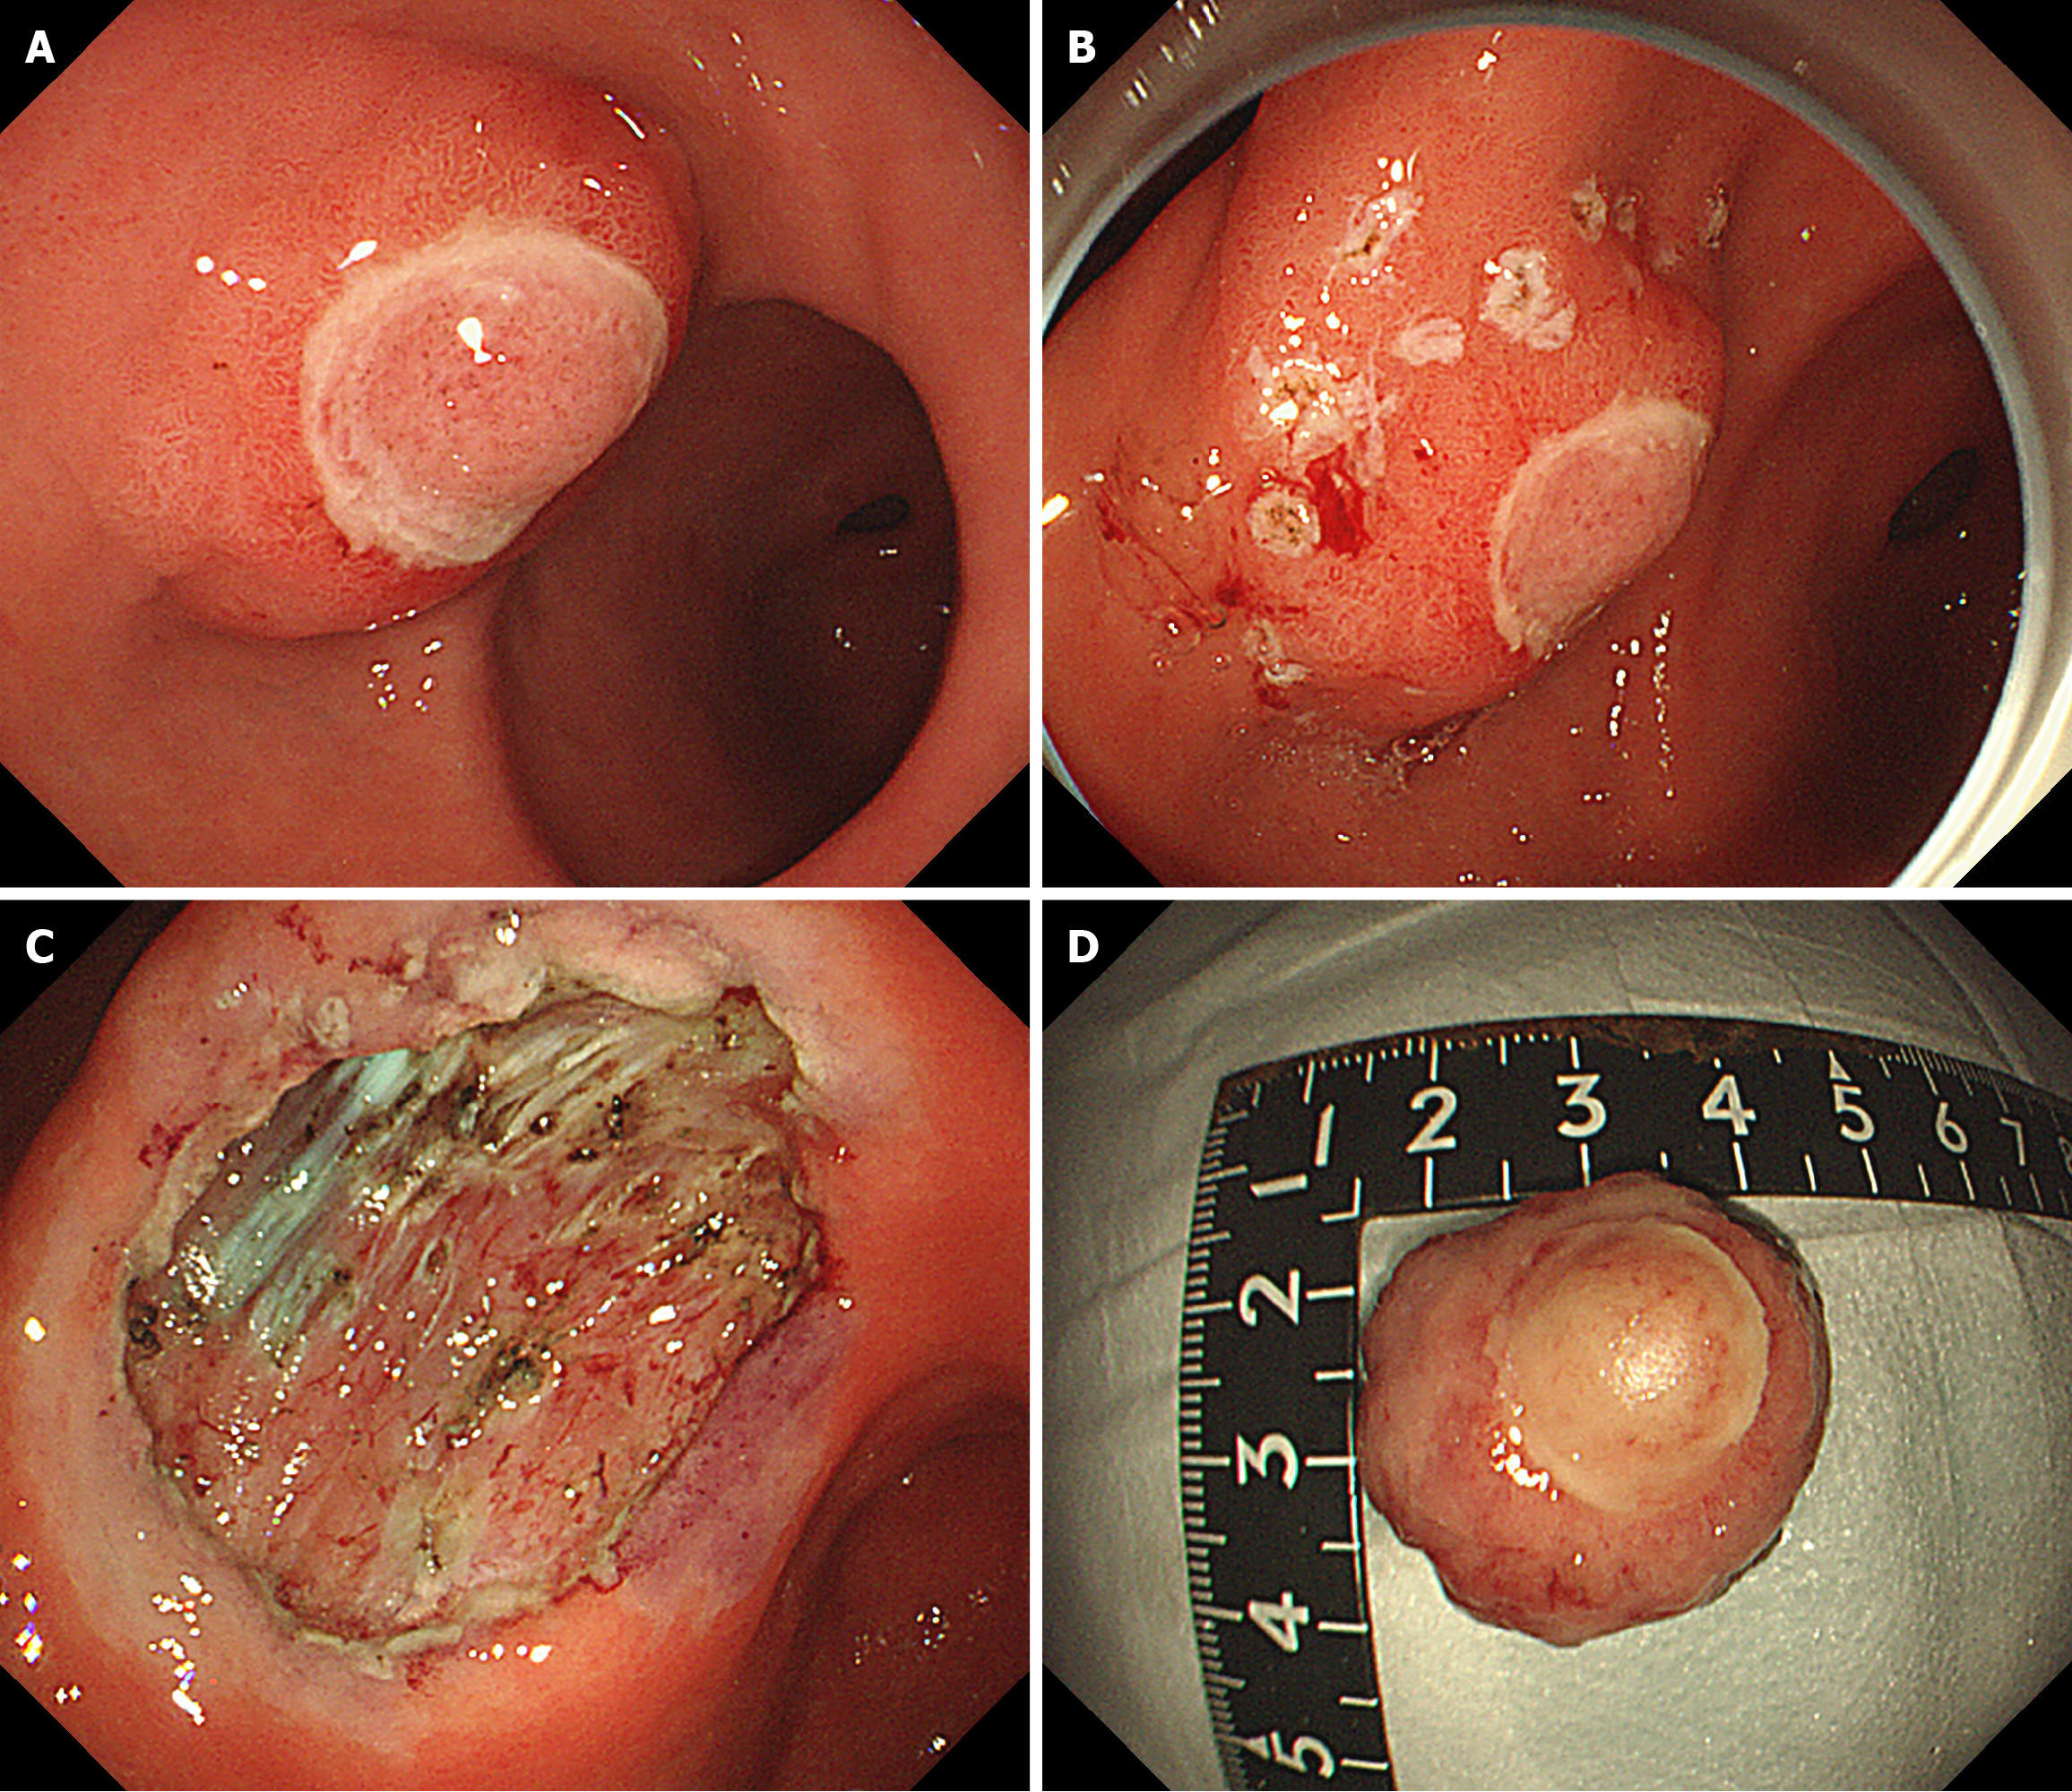

Figure 4 Endoscopic submucosal dissection.

A: The diameter of the submucosal bulge on the anterior wall of the gastric antrum was approximately 2.5 cm, with ulceration of the surface mucosa; B: Lateral mark of lesion; C: Postoperative wound; D: Postoperative specimen.